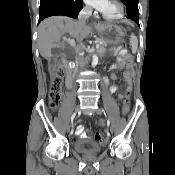

52 歲男性患者,因為發燒,右上腹悶痛來到急診,腹部電腦斷層如下圖所示,其可能的診斷為何?

本題圖片為腹部電腦斷層冠狀切面(coronal view)。影像所見:

- 中央管狀低密度結構:可見肝臟內及肝門部有明顯擴張的管狀低密度影,走向符合總膽管(common bile duct, CBD)及肝內膽管(intrahepatic bile ducts)的解剖位置,顯示膽道系統擴張(biliary dilatation)。

- 肝臟形態:肝臟大小尚可,未見明顯巨大低密度膿瘍腔,不符合肝膿瘍的典型表現。

- 膽囊區域:影像中未見膽囊壁明顯增厚或膽囊周圍積液的典型膽囊炎徵象。

- 腹主動脈及脊椎:可見正常解剖結構,用於影像定位。

整體影像最重要的發現為肝內外膽管擴張,結合患者發燒與右上腹疼痛,高度提示總膽管結石(choledocholithiasis)造成膽道阻塞並繼發急性膽道炎(acute cholangitis)。